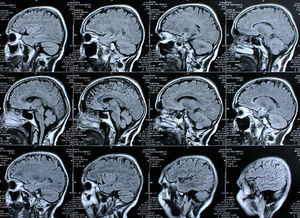

Gehirn-Scans: Heilung von Schädigungen als Ziel. Bild: pixelio.de, Rike